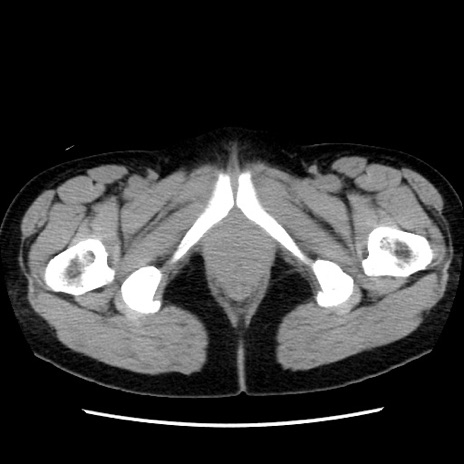

症例10(横断像)

【症例】 50歳代女性

【主訴】 腹痛

【現病歴】前日生レバーを食べた。今朝に排便あり。 昼前に突然発症の腹痛を生じ、当院救急外来を受診した。

【既往歴】 子宮筋腫にてで子宮全摘後

【身体所見】 意識清明、腹部:平坦、軟、下腹部やや左を中心に圧痛・反跳痛あり、筋性防御あり

【データ】WBC 7800、CRP 0.07